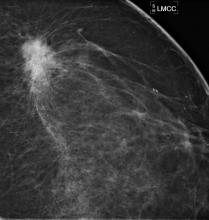

A study of breast cancers detected with screening mammography found that strong family history and dense breast tissue were commonly absent in women between the ages of 40 and 49 diagnosed with breast cancer. Results of the study were presented at the annual meeting of the Radiological Society of North America (RSNA).